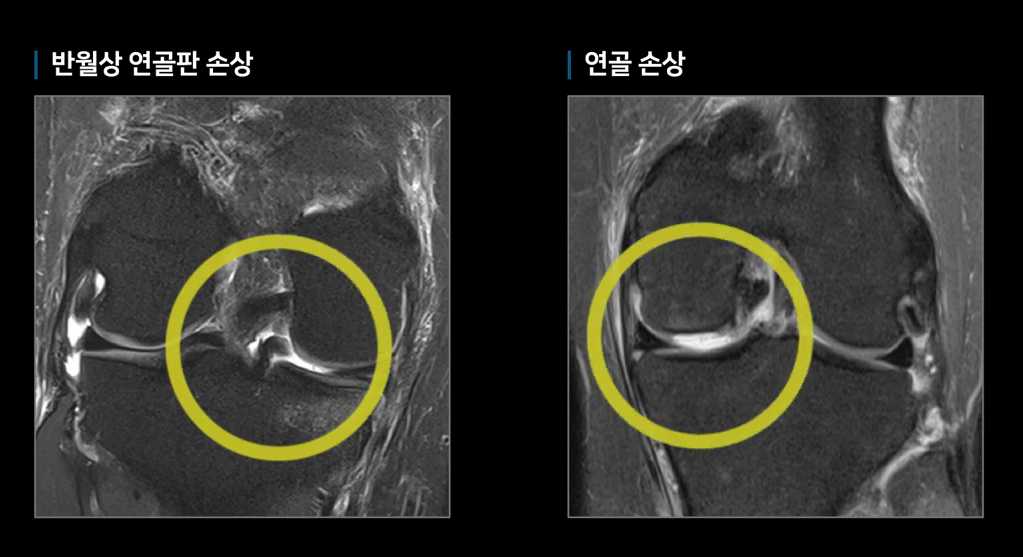

혼자서 하기보다는 두 사람이 같이 해보는 것이 좋습니다. 두 사람이 서로 마주보고 손을 마주 잡습니다. 진단을 받아볼 사람이 한쪽 무릎을 들고 다른 한쪽 다리로 중심축을 잡은 채 좌우 양쪽으로 움직여보는 것입니다. 한 다리를 진단해 본 다음에는 다리를 바꿔 다른 다리도 움직여봅니다. 이때 무릎에 불편한 느낌이 있거나 통증이 있다면, 초기 관절염을 의심해 볼 수 있습니다. 초기 관절염이 의심되면 병원에 가서 검사를 받아보는 것이 좋은데, 이 때 상황에 따라 권하는 것이 다를 수는 있으나, 꼭 고가의 MRI검사를 받지 않더라도, 엑스레이 검사만으로도 관절염의 진행상황을 알아볼 수 있으니, 의심이 될 때는 검사를 미리 받아 나의 상태를 전문가를 통해 정확하게 진단받는 것이 옳겠습니다. 통증이 심하거나 통증이 심하지 않더라도 무릎의 상태를 정확하게 파악하고자 때는 MRI검사를 받는 것이 정확합니다.

엑스레이 검사 MRI검사